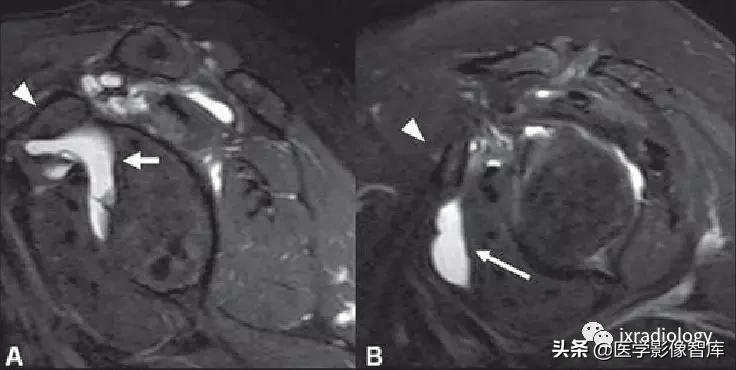

A图:(superior subscapularis recess):肩胛下肌上隐窝

B图:subcoracoid bursa:喙突下滑囊

箭头:subcoracoid bursa:喙突下滑囊积液

箭:退变和内侧脱位的肱二头肌长头肌腱